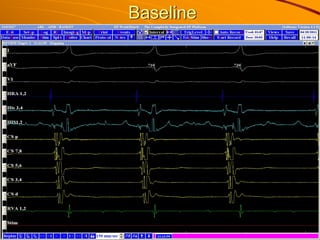

This 23-year-old woman presented with palpitations when carrying heavy materials and was found to have paroxysmal supraventricular tachycardia. She received adenosine and verapamil which terminated the arrhythmia. An electrophysiology study found atrioventricular reentrant tachycardia using an accessory pathway. Radiofrequency catheter ablation was performed and successfully eliminated conduction over the left posteroseptal and left lateral accessory pathways. She was diagnosed with manifest Wolff-Parkinson-White syndrome status post successful ablation.